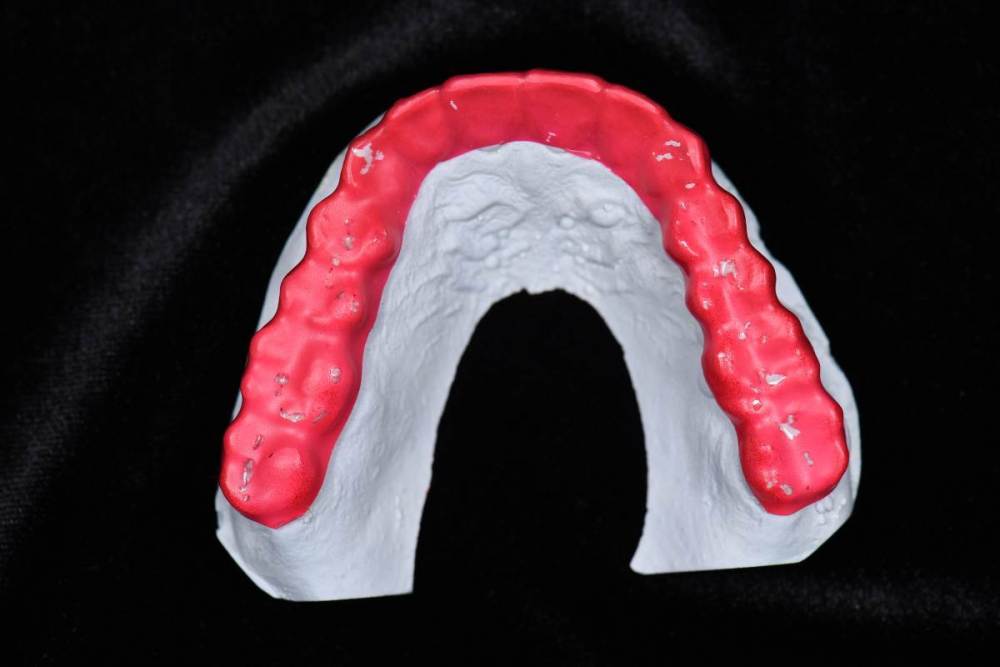

До:

DSC_5213.thumb.JPG.6e86a6f23d4a3b351481153ff65ce690.JPG

DSC_5219.thumb.jpg.8c7bd392d78063bb07c5c97fce7c79af.jpg

695024850_.thumb.jpg.dee291f8ad325f6772d1bf6981bd13c4.jpg62927585_.thumb.jpg.daa94f744be7e20b7cd9470a76746d10.jpg